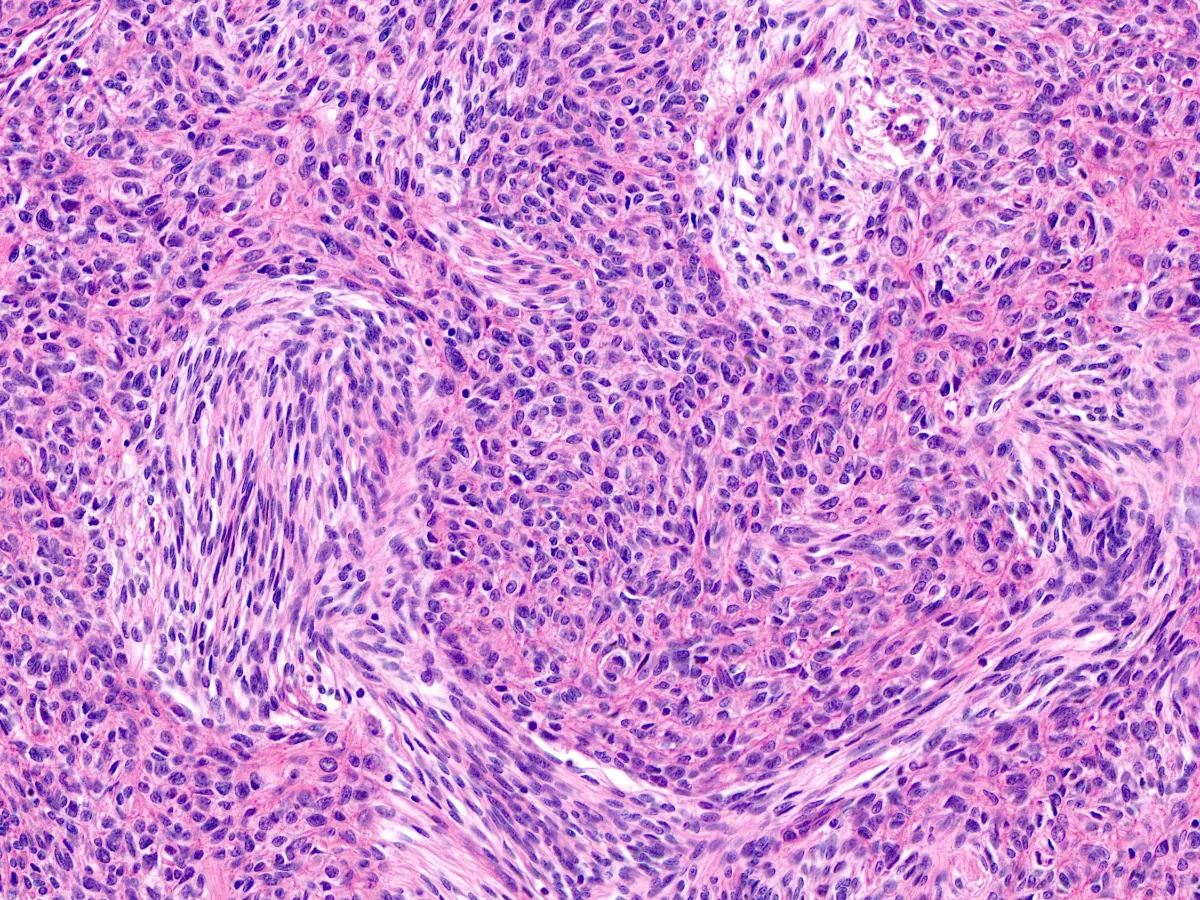

3. HE 20x

Diagnóstico: Timoma metaplásico

- Se trata de un tumor bifásico de origen tímico compuesto por islas de células epiteliales y células fusiformes de bajo grado citológico, con áreas de transición de gradual a abrupta entre ambos componentes.

- Con técnicas de inmunohistoquímica las células epiteliales expresan CK, p63/p40 y EMA, así como negatividad para Vimentina. Las áreas fusocelulares, por el contrario, expresan Vimentina, positividad focal o negatividad para Citoqueratinas y EMA y negatividad para p63 y p40. Ambos componentes son negativos para CD5, CD20, CD34 y CD117 (c-kit). El índice de proliferación Ki67 es bajo en ambos componentes (<5%).

- Entre los diagnósticos diferenciales se incluye el carcinoma sarcomatoide, aunque este presenta de forma invariable un componente estromal de alto grado, con marcada atipia nuclear, mitosis atípicas y ocasionalmente diferenciación heteróloga.